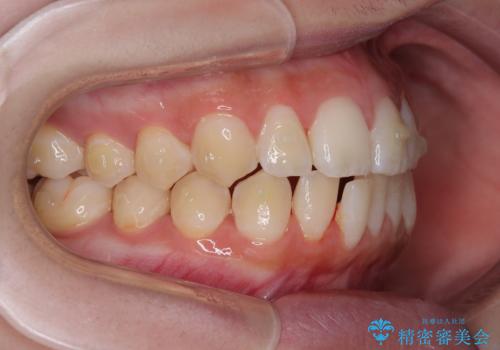

- 今回は「下の前歯のデコボコを治したい」と来院された患者様の症例をご紹介します。

診察してみると、下の前歯が並ぶためのスペースが足りないことが、歯並びがデコボコしている原因でした。

そこで今回は、以下の2つの方法を組み合わせて治療を行いました:

下の前歯の歯と歯の間をわずかに削ってスペースを作る(IPR)

奥歯を後ろに動かして、前歯が並ぶためのスペースを確保する

この計画により、デコボコだった下の前歯はしっかりと並び、わずか1年で治療を終えることができました